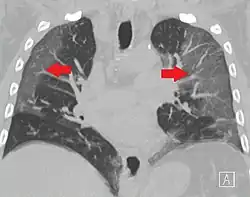

High-resolution CT image showing ground-glass opacities in the periphery of both lungs in a patient with COVID-19 (red arrows). The adjacent normal lung tissue with lower attenuation appears as darker areas.

Ground-glass opacity is among the most common imaging findings in patients with confirmed COVID-19.[16][17] One systematic review found that among patients with COVID-19 and abnormal lung findings on CT, greater than 80% had GGOs, with greater than 50% having mixed GGOs and consolidation.[16] GGOs with mixed consolidation has most often been found in elderly populations.[18] Several studies have described a pattern among initial, intermediate, and hospital discharge imaging findings in the disease course of COVID-19. Most commonly, initial CT imaging reveals bilateral GGOs at the periphery of the lungs. During initial stages, this is most often found in the lower lobes, although involvement of the upper lobes and right middle lobe has also been reported early in the disease course.[16][18] This is in contrast to the two similar coronaviruses, SARS and MERS, which more commonly involve only one lung on initial imaging.[19][20] As the COVID-19 infection progresses, GGOs typically become more diffuse and often progress to consolidation.[11][18] This is sometimes accompanied by the development of a crazy paving pattern and interlobular septal thickening.[18] In many cases the most severe pulmonary CT abnormalities occurred within 2 weeks after symptoms began.[17] At this point, many individuals begin showing resolution of consolidation and GGOs as symptoms improve. However, some patients have worsening symptoms and imaging findings, with further increase in septal thickening, GGOs, and consolidation. These patients may develop lung "white-out" with progression to acute respiratory distress syndrome (ARDS) requiring treatment escalation.[17][21]

Preliminary reports have shown many patients have residual GGOs at time of discharge from the hospital. Due to the novelty of COVID-19, large studies investigating the long-term pulmonary CT changes have yet to be completed. However, long-term pulmonary changes have been seen in patients after recovery from SARS and MERS, suggesting the possibility of similar long-term complications in patients who have recovered from acute COVID-19 infection.[22]